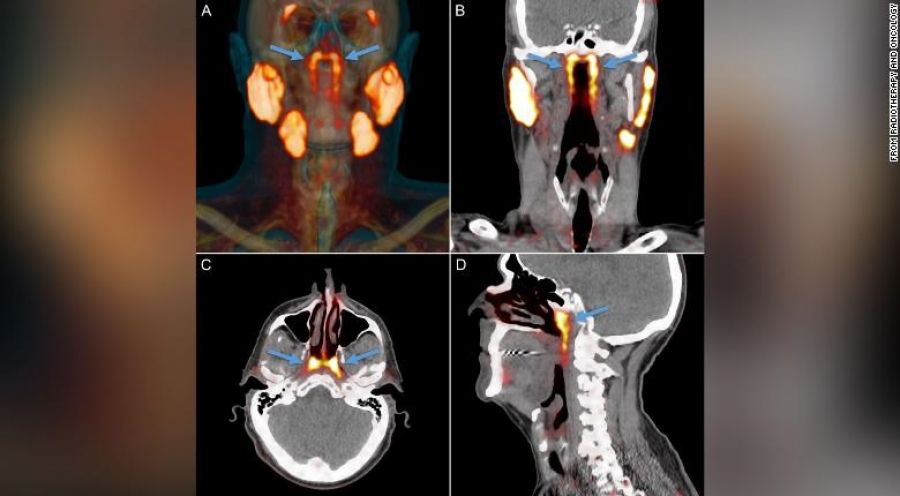

Dijeron que han descubierto un par de glándulas previamente pasadas por alto que están escondidas en nuestros cráneos donde se encuentran la cavidad nasal y la garganta.

Los investigadores médicos encontraron por primera vez la parte del cuerpo, que proponen nombrar glándulas tubarias, durante una exploración diseñada para buscar crecimientos tumorales.

Luego, los científicos observaron escaneos de la cabeza y el cuello de otras 100 personas que estaban tratando por cáncer de próstata y diseccionaron dos cadáveres, uno masculino y otro femenino. Todos tenían un juego.

Las glándulas no se pueden ver con métodos convencionales de imágenes médicas como ultrasonido, tomografías computarizadas o imágenes de resonancia magnética, dijeron los autores del estudio.

La «entidad desconocida» solo se identificó cuando los médicos utilizaban un tipo de exploración nuevo y avanzado llamado PSMA PET/CT que se ha utilizado para detectar la propagación del cáncer de próstata. PSMA PET es la abreviatura de la obtención de imágenes de antígeno de membrana específico de la próstata mediante tomografía por emisión de positrones.